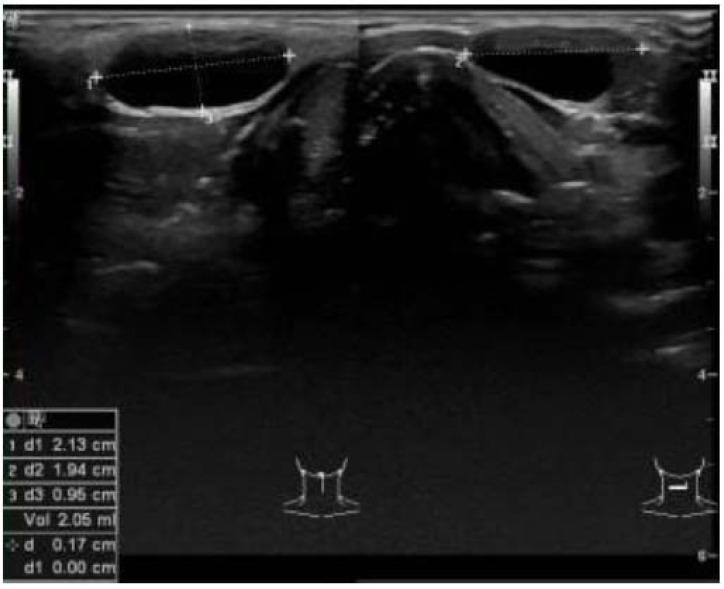

Embryologic developmental variants of the thyroid and parathyroid glands may cause cervical anomalies that are detectable in ultrasound examinations of the neck. For some of these developmental variants, molecular genetic factors have been identified. Ultrasound, as the first-line imaging procedure, has proven useful in detecting clinically relevant anatomic variants. The aim of this article was to systematically summarize the ultrasound characteristics of developmental variants of the thyroid and parathyroid glands as well as ectopic thymus and neck cysts. Quantitative measures were developed based on our findings and the respective literature. Developmental anomalies frequently manifest as cysts that can be detected by cervical ultrasound examinations. Median neck cysts are the most common congenital cervical cystic lesions, with a reported prevalence of 7% in the general population. Besides cystic malformations, developmental anomalies may appear as ectopic or dystopic tissue. Ectopic thyroid tissue is observed in the midline of the neck in most patients and has a prevalence of 1/100,000 to 1/300,000. Lingual thyroid accounts for 90% of cases of ectopic thyroid tissue. Zuckerkandl tubercles (ZTs) have been detected in 55% of all thyroid lobes. Prominent ZTs are frequently observed in thyroid lobes affected by autoimmune thyroiditis compared with normal lobes or nodular lobes (P = 0.006). The correct interpretation of the ultrasound characteristics of these variants is essential to establish the clinical diagnosis. In the preoperative assessment, the identification of these cervical anomalies via ultrasound examination is indispensable.

胚胎发育过程中甲状腺和甲状旁腺的变异可能导致颈部超声检查可发现的颈部异常。对于其中一些发育变异,已经确定了分子遗传因素。超声作为一线成像程序,已被证明在检测临床相关解剖变异方面非常有用。本文旨在系统总结甲状腺和甲状旁腺、胸腺异位和颈部囊肿等发育变异的超声特征。根据我们的发现和相关文献制定了定量指标。发育异常通常表现为可通过颈部超声检查检测到的囊肿。中位颈部囊肿是最常见的先天性颈部囊性病变,在普通人群中的报道患病率为 7%。除了囊性畸形,发育异常也可能表现为异位或异位组织。异位甲状腺组织在大多数患者的颈部中线观察到,患病率为 1/100,000 至 1/300,000。舌甲状腺占异位甲状腺组织的 90%。在所有甲状腺叶中,已检测到 55%的 Zuckerkandl 结节 (ZTs)。与正常叶或结节叶相比,自身免疫性甲状腺炎受累的甲状腺叶中常观察到明显的 ZTs(P=0.006)。正确解读这些变异的超声特征对于建立临床诊断至关重要。在术前评估中,通过超声检查识别这些颈部异常是必不可少的。